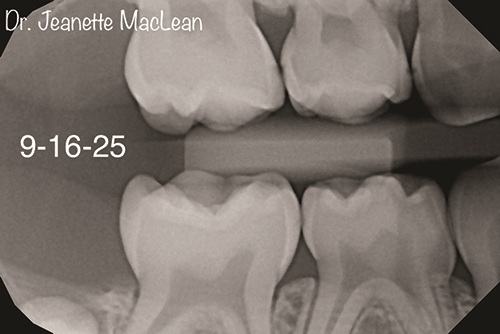

Figs. 3a and 3b: Five-month follow-up BWs (DEXIS Titanium imaging).

A four-year-old patient presents with his mother for a second opinion exam. The mother of the child expresses concern for a surgical treatment plan presented by another pediatric dentist, since her child has no visible decay and is asymptomatic. Patient’s aunt, a dental hygienist who lives out of state, suggests they see me for a second opinion to determine whether a less invasive approach could be taken. The child’s mother had never heard of silver diamine fluoride but was extremely grateful for the nonsurgical option and agreed to have it applied the same day. Patient returns five months later, six months since his last prophy at the previous provider. New bite wings show that the incipient lesions are stable, and SDF is reapplied. Patient’s little sister is also seen for a new patient exam. Both parents attend this visit and express their extreme gratitude for the noninvasive treatment option I gave them, and state that they have been telling their friends with children about their experience.